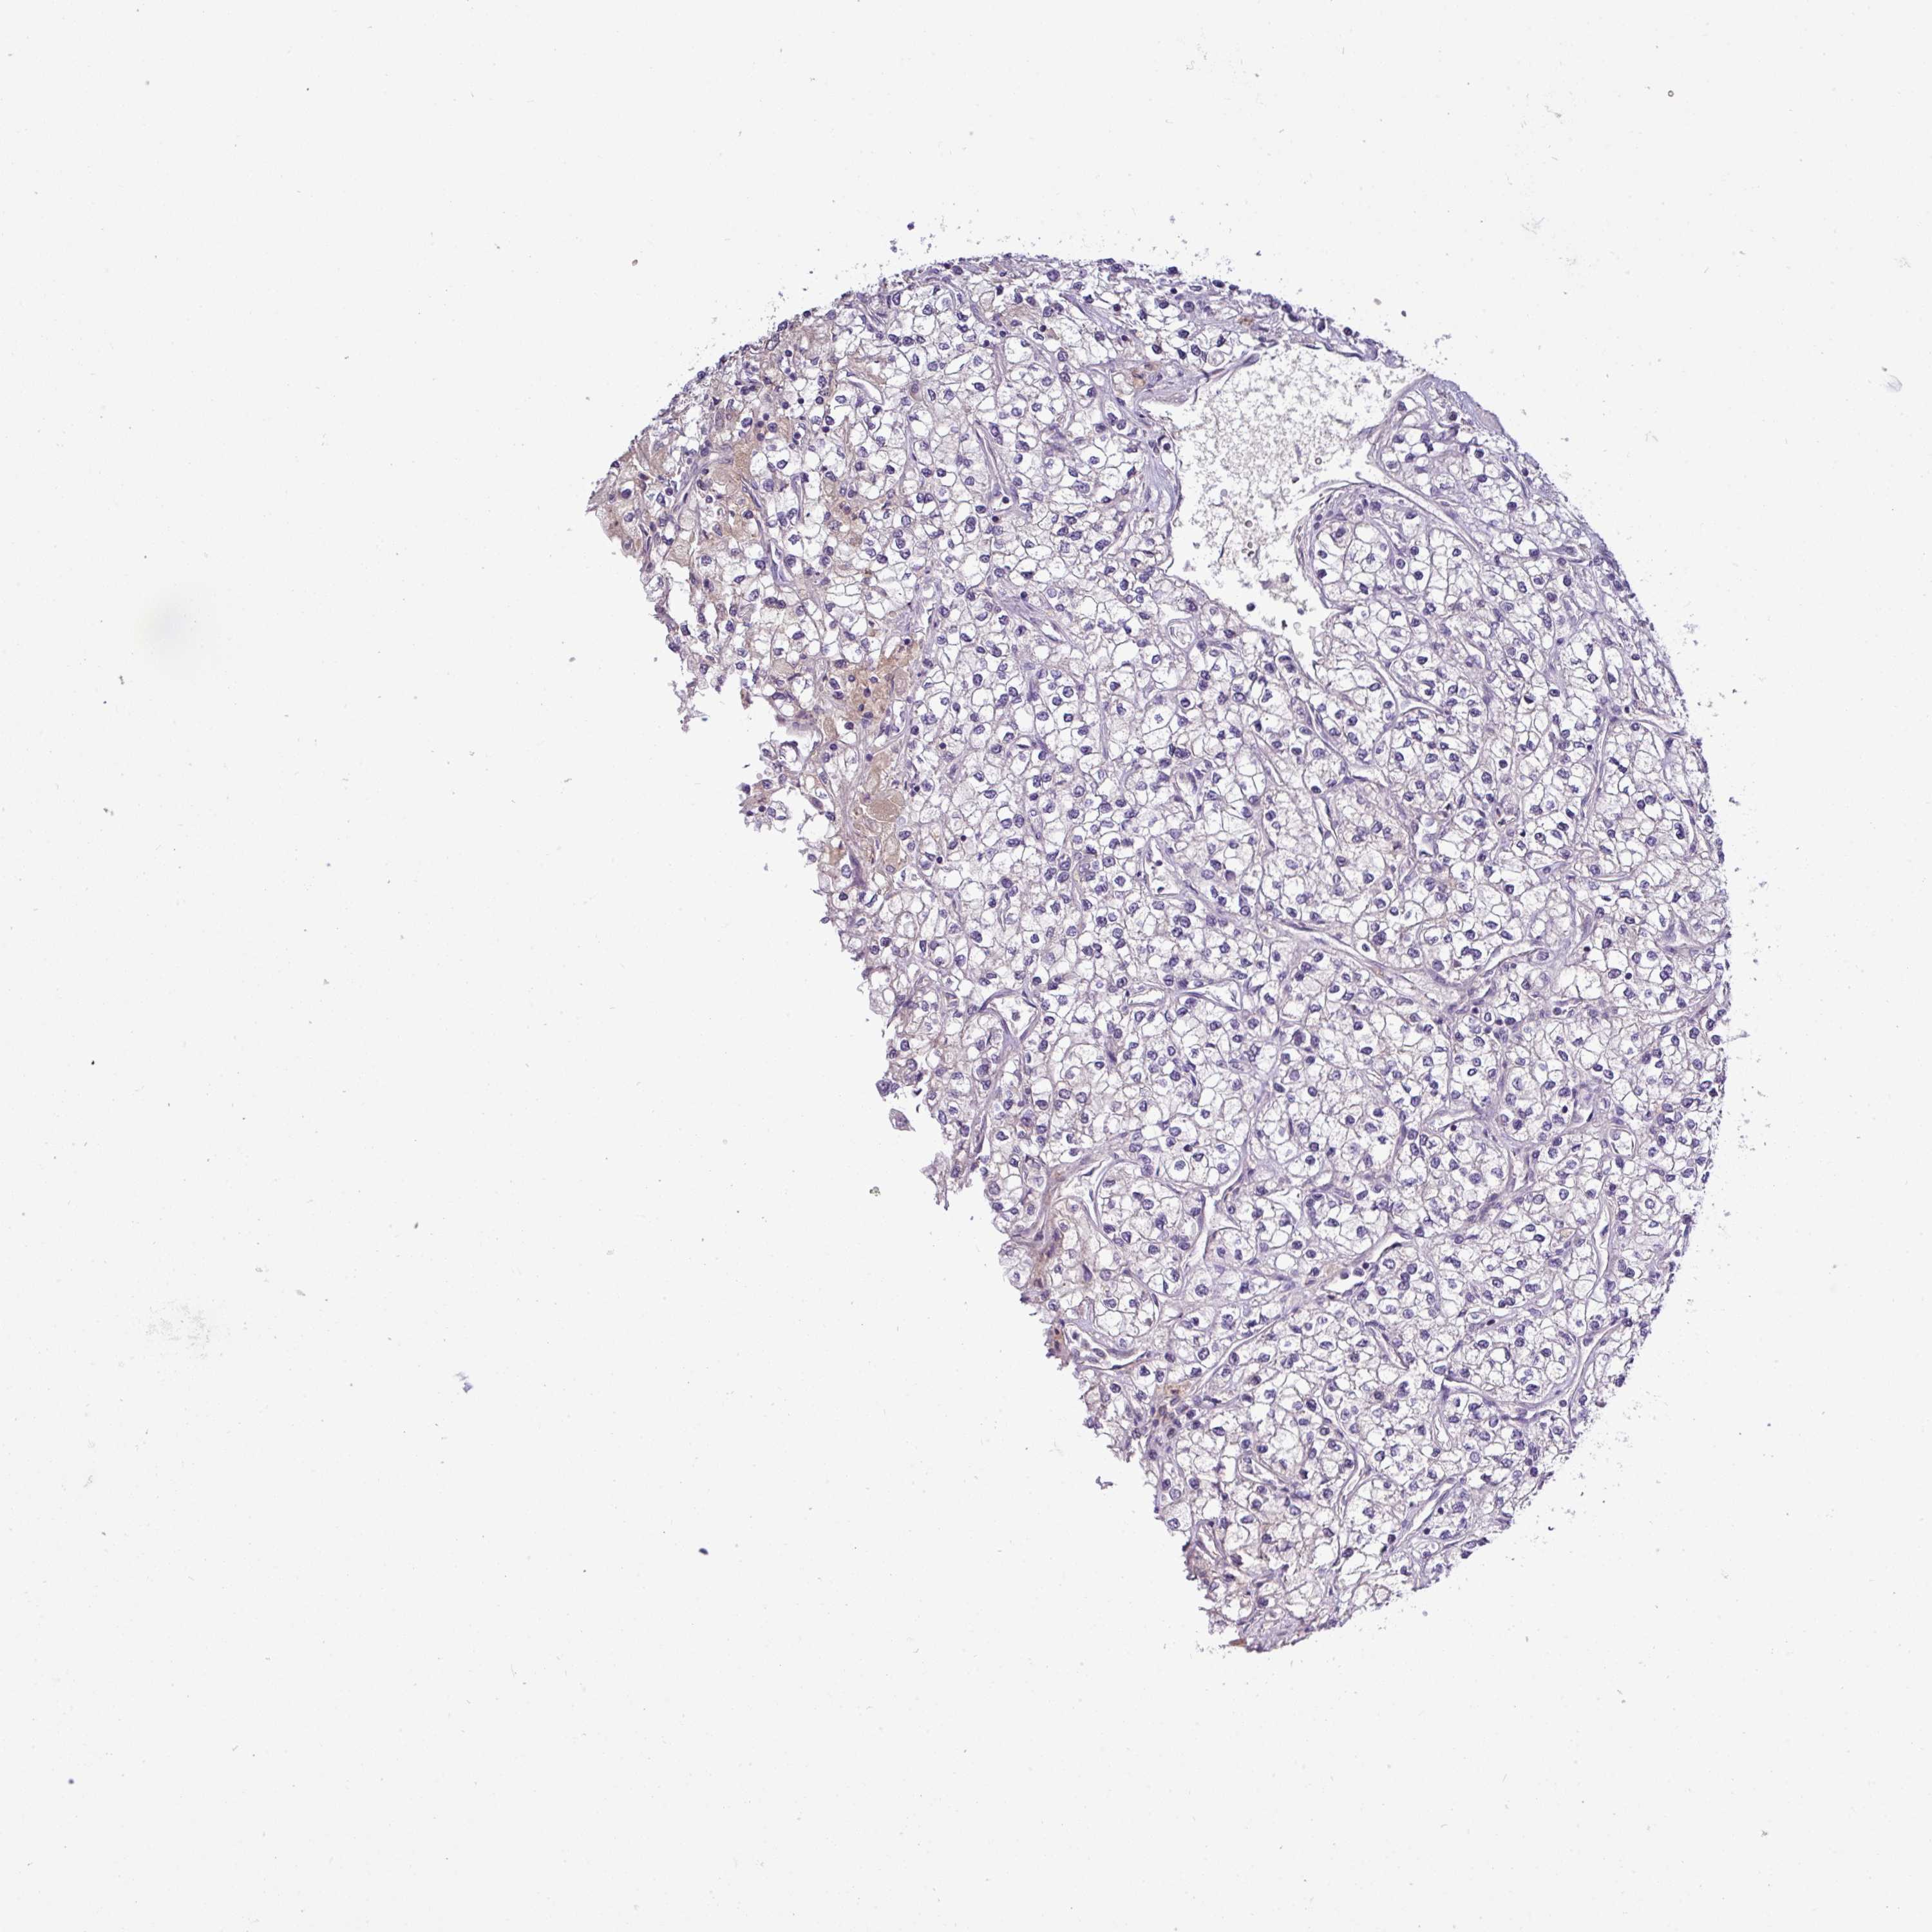

KIDNEY RENAL CLEAR CELL CARCINOMA (VALIDATION) - Interactive survival scatter ploti

The Survival Scatter plot shows the clinical status (i.e. dead or alive) for all individuals in the patient cohort, based on the same data that underlies the corresponding Kaplan-Meier plots. Patients that are alive at last time for follow-up are shown in blue and patients who have died during the study are shown in red.

The x-axis shows the expression levels (FPKM) of the investigated gene in the tumor tissue at the time of diagnosis. The y-axis shows the follow-up time after diagnosis (years). Both axes are complimented with kernel density curves demonstrating the data density over the axes. The top density plot shows the expression levels (FPKM) distribution among dead (red) and alive patients (blue). The right density plot shows the data density of the survived years of dead patients with high and low expression levels respectively, stratified using the cutoff indicated by the vertical dashed line through the Survival Scatter plot. This cutoff is automatically defined based on the FPKM cutoff that minimizes the p-score. The cutoff can be changed by dragging the vertical line or by entering a cutoff value in the square labeled "Current cut-off".

Under the Survival Scatter plot the p-score landscape (black curve; left axis) is shown together with dead median separation (red curve; right axis). Dead median separation is the difference in median mRNA expression between patients who have died with high and low expression, respectively. It is calculated as follows: median FPKM expression of dead patients with high expression - median FPKM expression of dead patients with low expression. This is intended to aid the user in visually exploring custom cutoffs and the associated p-scores and dead median separation.

& Survival analysisi

Kaplan-Meier plots summarize results from analysis of correlation between mRNA expression level and patient survival. Patients were divided based on level of expression into one of the two groups "low" (under cut off) or "high" (over cut off). X-axis shows time for survival (years) and y-axis shows the probability of survival, where 1.0 corresponds to 100 percent.

TMEM62 is not prognostic in Kidney Renal Clear Cell Carcinoma (validation)

: 9.57

Average pTPM 12.7

Number of samples 100